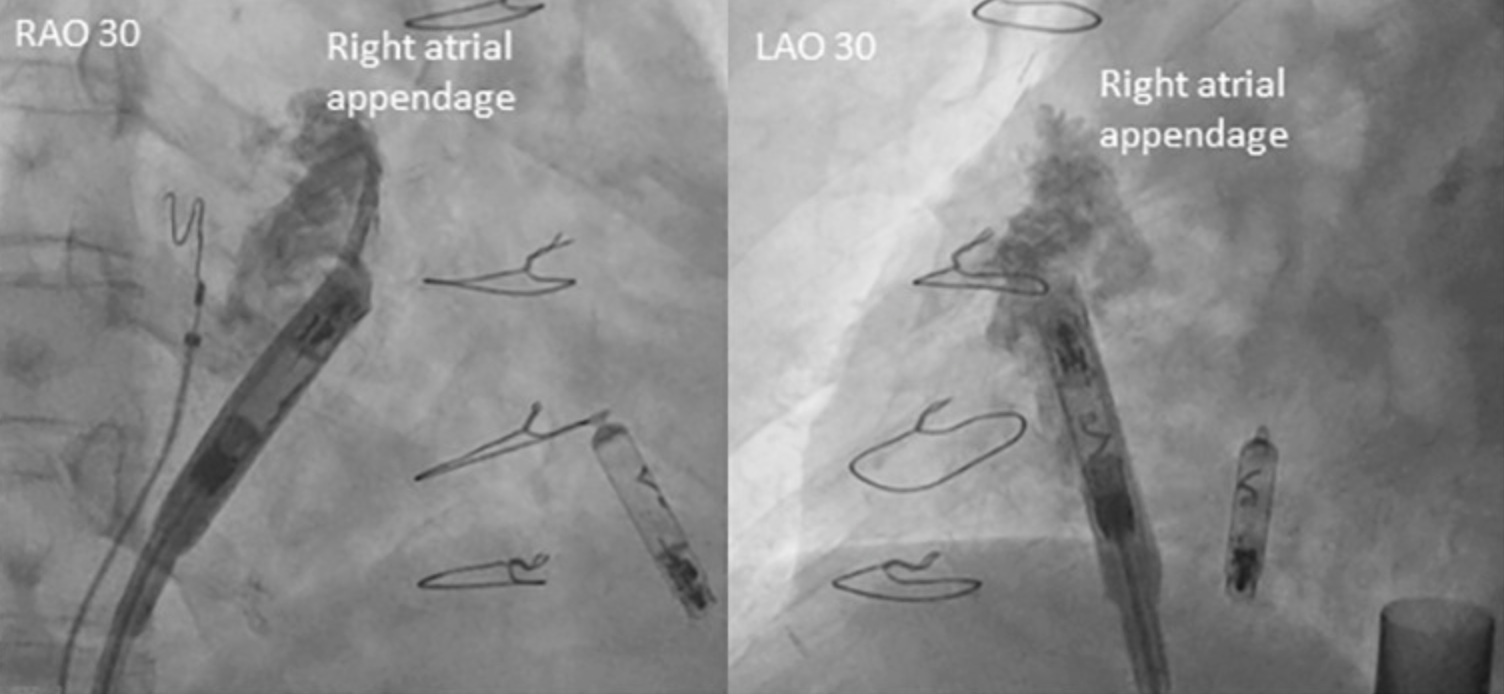

• 在术中,术者按照标准植入流程植入了心室无导线起搏器:导管跨过三尖瓣后,通过造影明确了低位间隔的最佳植入位置,随后通过Mapping标测确定了最佳旋入点,后进行旋入固定;心房无导线起搏器同样按标准植入流程植入于右心耳基底部(图1、2、3)。

图2 心房无导线起搏器植入时RAO和LAO造影